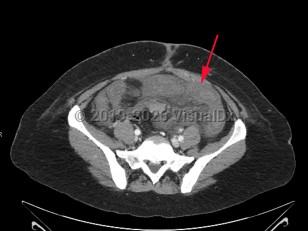

Risk factors for mesenteric ischemia reflect the pathophysiologic mechanisms for each variant: SMA embolism, SMA thrombosis, mesenteric vein thrombosis, and NOMI. Commonly associated conditions include underlying cardiac disease (ie, atrial fibrillation, congestive heart failure with reduced ejection fraction, valvular disorders), hypertension, diabetes, hyperlipidemia, smoking, and hypercoagulable states. More rarely, those who have undergone recent endovascular aortic repair are at increased risk.